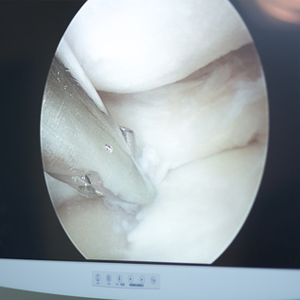

تنظير الكاحل:

- هو إجراء جراحي ليوم واحد فقط، يتم من خلال إحداث شق صغير جدًا (جراحة ثقب المفتاح)، مع تعافٍ سريع ونتائج ممتازة في معظم الحالات. يُعد تنظير الكاحل العلاج المفضل لحالات التهاب الغشاء الزليلي للكاحل، وتنخر العظم والغضروف (OCD)، والعديد من حالات الكاحل الأخرى. توفر عيادة العظام لدينا في مركز الدكتور رامي حمد أفضل جراحي العظام في دبي، والذين يتمتعون بخبرة واسعة في تنظير الكاحل، إلى جانب خدمات جراحة الطب الرياضي الأخرى التي نقدمها.

- تتضمن الجراحة عمل فتحتين بطول 4 مم لكل منهما، لإدخال كاميرا ألياف ضوئية بقطر 2.7 مم مع أدوات جراحية صغيرة تساعد على إجراء العملية داخل مفصل الكاحل.

- يساعد تنظير الكاحل على تشخيص الحالة الطبية وعلاجها في الوقت نفسه.